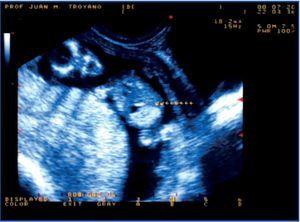

We had the opportunity of studying a child, currently three years old, who was referred by his paediatrician when he was five months old, after an episode of gross haematuria, which revealed the presence of a stone in the nappy. It was the first child of non-consanguineous parents, without any previous significant pathology, but with a history of renal colic on the paternal side of the family. Ultrasound foetal studies during pregnancy revealed a colon hyperechogenicity without other intestinal abnormalities (Figures 1 and 2), and a slightly increased nuchal luminescence, with no other findings of interest. As a result, a sweat test was performed at birth to rule out cystic fibrosis and the result was normal.

This is an early clinical presentation of cystinuria, reflecting the high lithogenic capacity of this condition. The particularity of the case is that the prenatal ultrasound found hyperechogenicity of the colon secondary to cystine crystal deposition. This form of presentation of cystinuria was described in 20063 and was subsequently confirmed.4 The explanation for this finding is that the cystine crystals are formed in the foetal kidney, they enter the amniotic fluid and are then swallowed. The ultrasound finding of the foetal hyperechogenic colon has been traditionally related to cystic fibrosis, which was why the studies needed to rule out the disease were performed at birth. The negative result and early clinical symptoms led to the diagnosis. Knowledge of this association may facilitate an early diagnosis of the disease, thus establishing an appropriate treatment.

Figure 2. A similar situation early in the second trimester